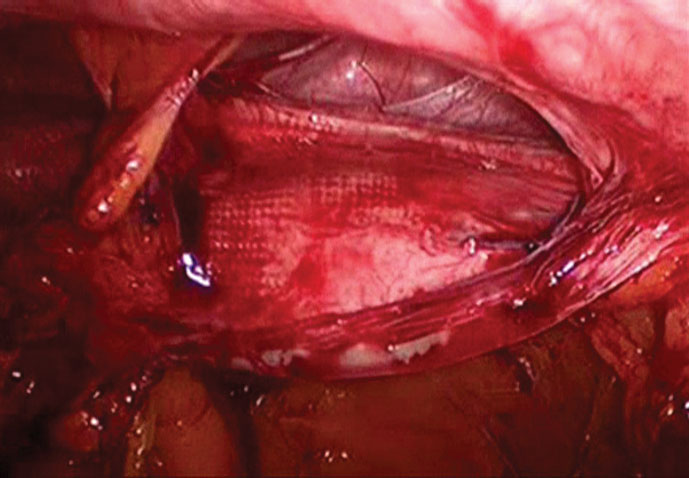

Video 9 shows a folded and contracted PTFE/polypropylene composite mesh that has allowed for a recurrent hernia. With the mesh folded, the macroporous side of the mesh is exposed to the bowel and bowel can be seen adherent to the folded and contracted mesh. (Figure 3)